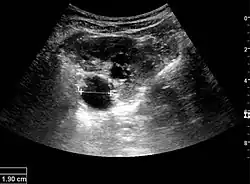

Figure 5. Simple renal cyst with posterior enhancement in an adult kidney. Measurement of kidney length on the US image is illustrated by '+' and a dashed line.[1]

Figure 6. Complex cyst with thickened walls and membranes in the lower pole of an adult kidney. Measurements of kidney length and the complex cyst on the US image are illustrated by '+' and dashed lines.[1]